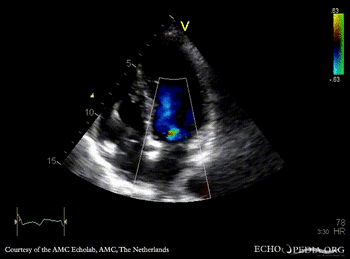

E00506.gif E00507.gif

A3CH with Color Doppler: high velocity turbulent flow in LVOT A4CH with Color Doppler: high velocity turbulent flow in LVOT and in the middle of left ventricle